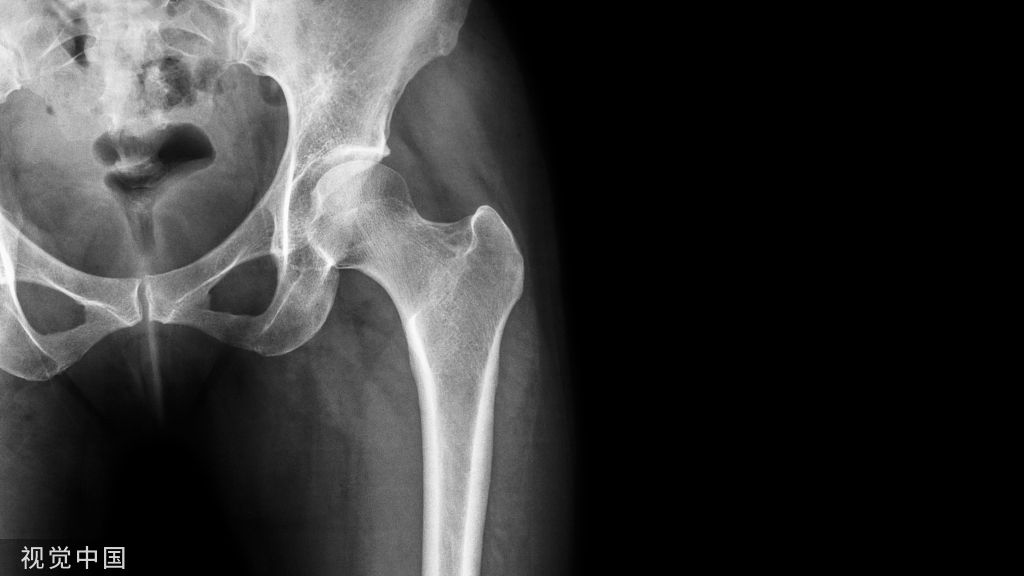

FAI影像学检查前后位片:可见股骨头不同程度的手枪柄样畸形侧位片: 观股骨头颈交界处骨性隆起;CE角﹥40°;髋臼后倾畸形;股骨颈的囊性变

FAI影像学检查CT: 冠状位可见髋臼后倾股骨颈轴位可见头颈交界处骨性隆起α角增大,股骨颈偏心距异常

FAI:齿轮型(cam-type )影像:股骨头、颈间的凹陷不足,可伴局部的骨质增生、硬化、囊变部位:前外股骨头、颈交界区